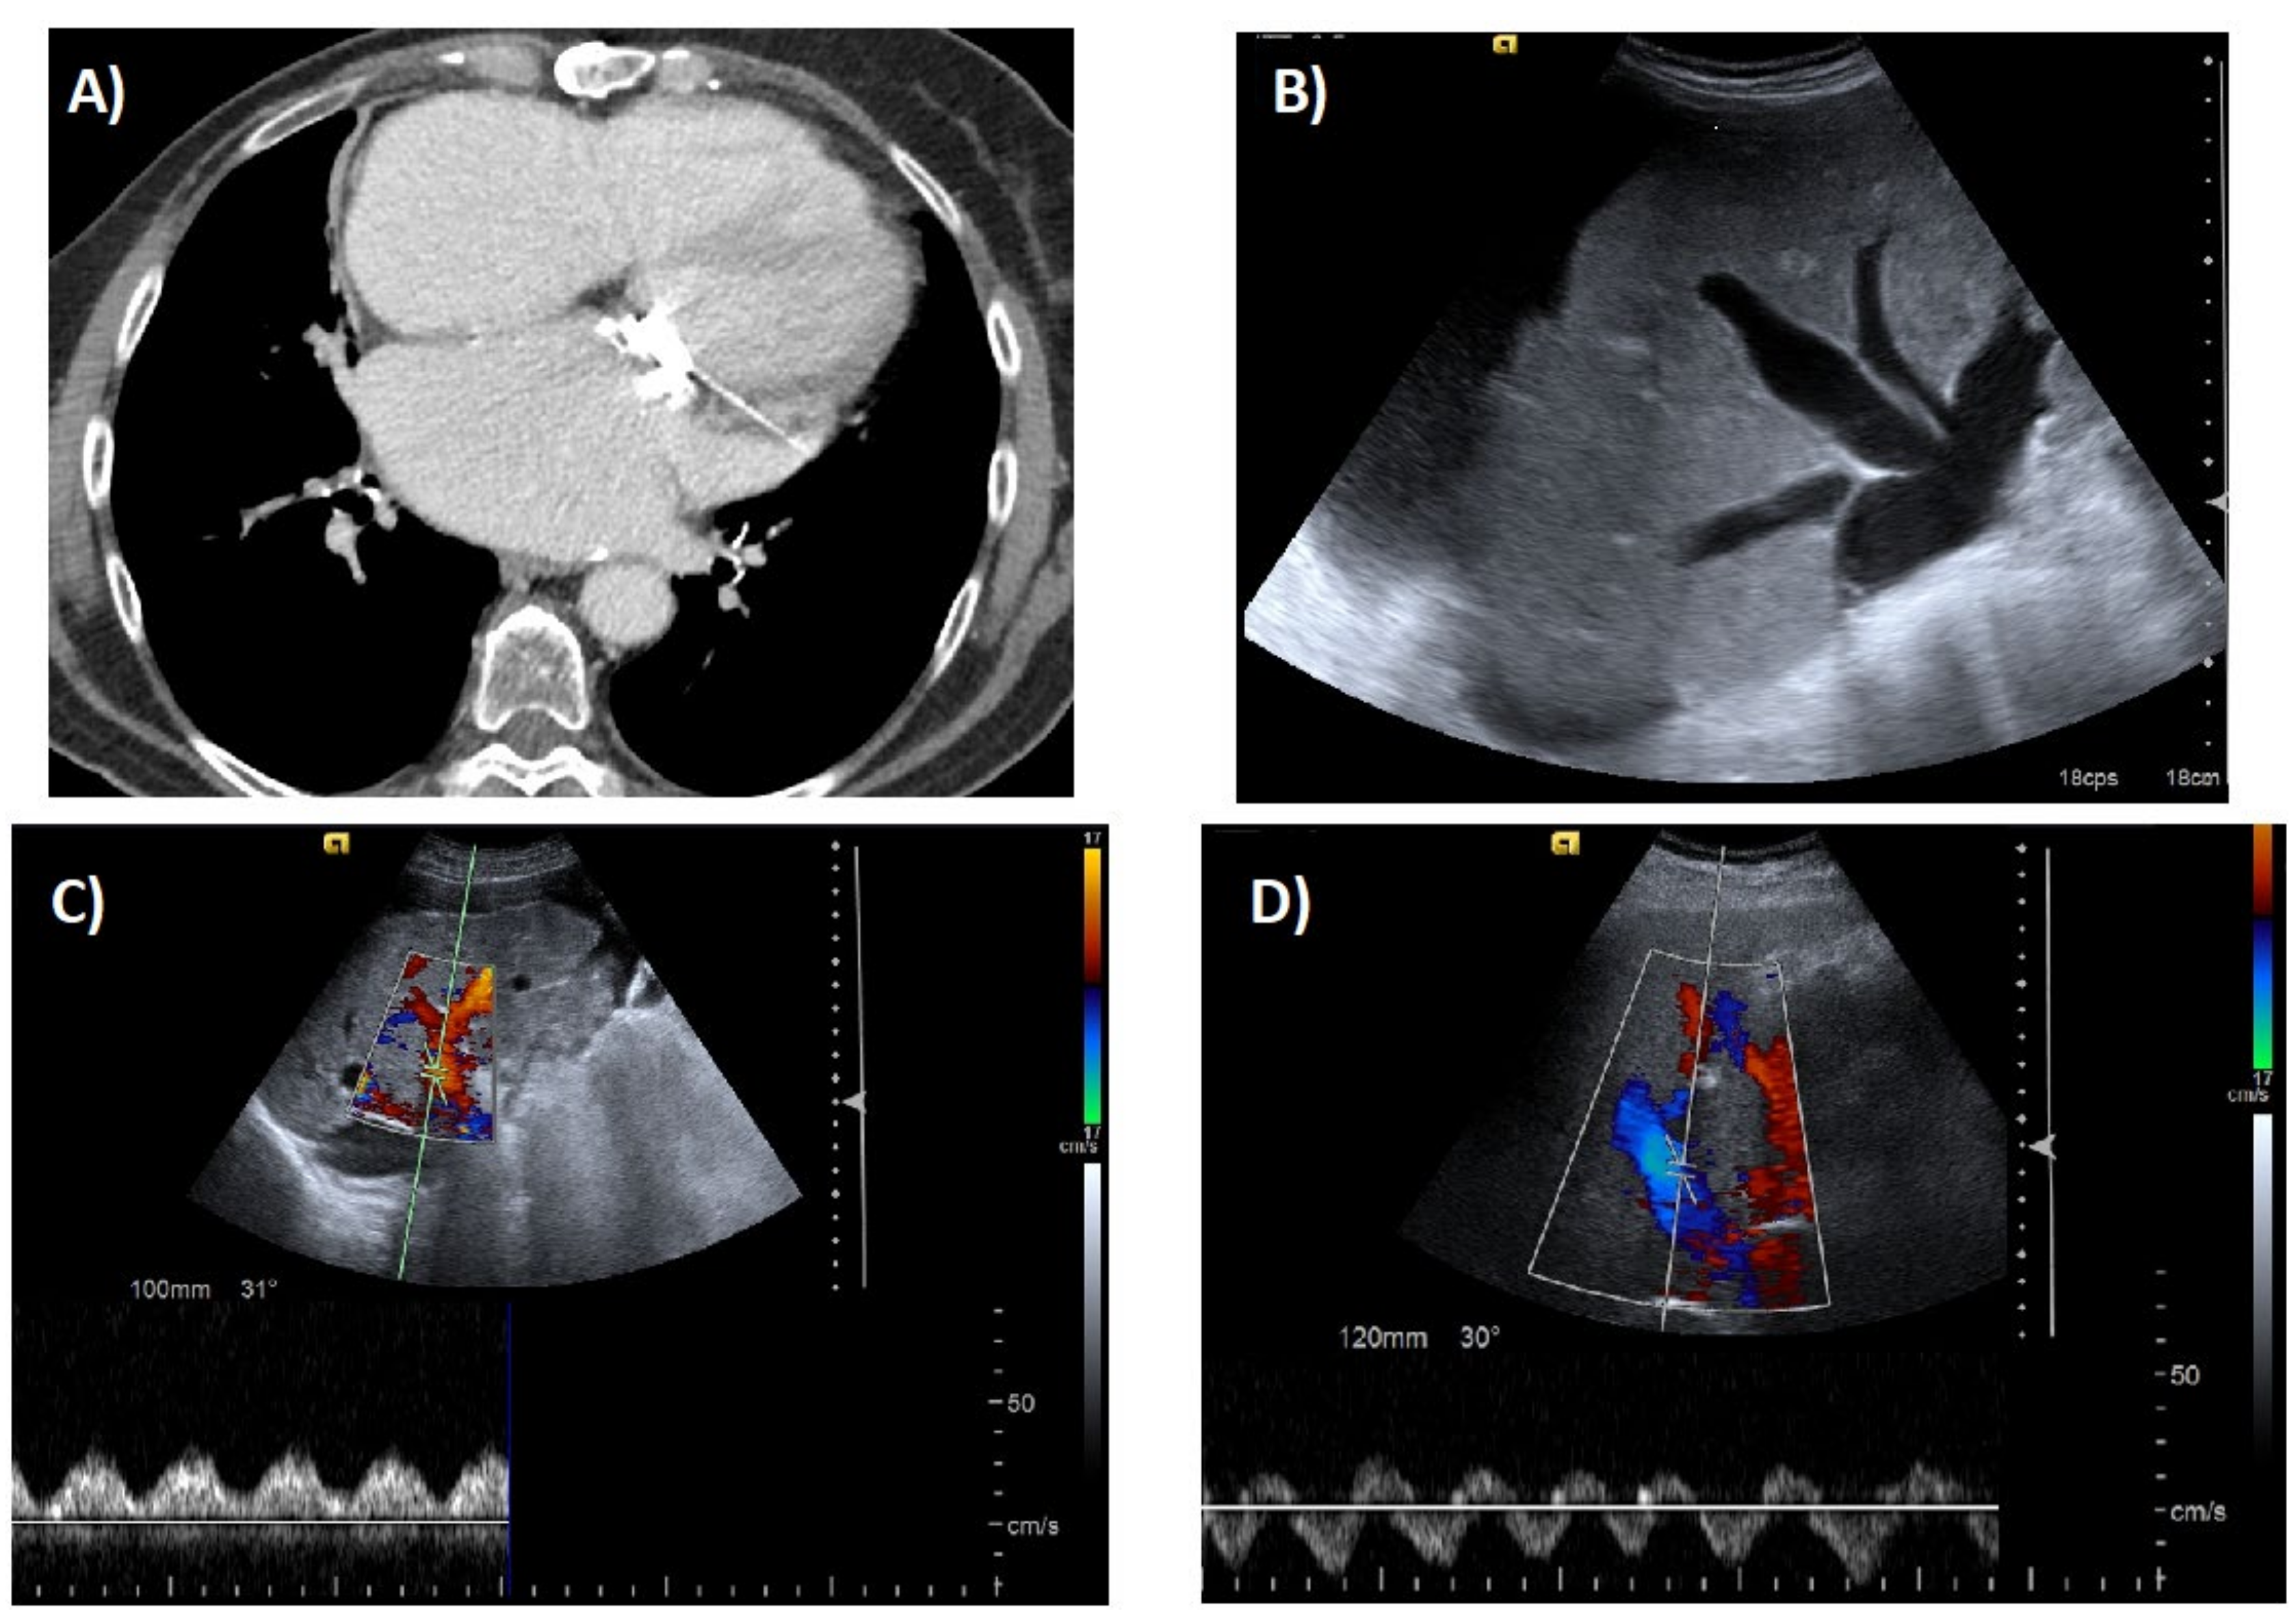

6. Imaging Tests

- Morales, A.; Hirsch, M.; Schneider, D.; González, D. Congestive hepatopathy: The role of the radiologist in the diagnosis. Diagn. Interv. Radiol. 2020. [Google Scholar] [CrossRef] [PubMed]

- Wells, M.L.; Venkatesh, S.K. Congestive hepatopathy. Abdom. Radiol. 2018, 43, 2037–2051. [Google Scholar] [CrossRef] [PubMed]